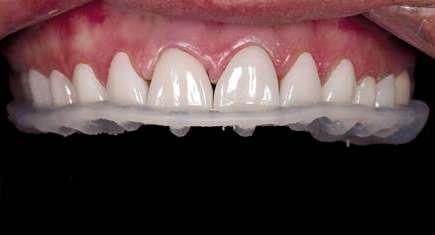

En la arcada superior por el contrario se decidió poner unas carillas de disilicato para poder cubrir las expectativas de la paciente y ajustar el color al que ella deseaba, bajando casi en 5 tonos el color final. Se planificaron preparaciones digitales conservadoras.

La tecnología digital permite lograr el equilibrio de espesores ideal para cada caso, así como un eje de inserción adecuado. Todo esto permite dar una garantía de longevidad a las restauraciones planificadas.

En este caso se realizó una preparación previa a la preparación guiada en los márgenes y zonas interproximales, para camuflar el sustrato y dar una correcta inserción; y posteriormente se utilizaron unas guías de tallado diseñadas digitalmente para obtener los resultados precisos y predecibles que requería el caso.

La preparación previa junto a la preparación guiada, resultaron en un equilibrio ideal para los espesores mínimos que requería el caso. Se realizó una prueba en seco para valorar el ajuste final de las restauraciones.

Para cementar las carillas y evitar movimientos no controlados y una incorrecta cementación, utilizaremos una guía de posicionamiento simultáneo, esta guía no es de cementación en bloque ya que las carillas están perfectamente individualizadas. Únicamente sirven para llevar a la boca del paciente las carillas y cementarlas de una forma 100% segura, evitando el estrés que genera un posible movimiento durante la cementación y acelerando los tiempos de trabajo.

Consiguiendo así una perfecta adaptación de los márgenes de las restauraciones y la sensación de naturalidad e integración que se observa en la imagen final.

Como se puede observar en la imagen comparativa, la planificación se reproduce de una forma fiel a lo que se había planificado y aceptado por la paciente. Por tanto, no es una técnica susceptible al operador, que se realiza controlando mucho mejor los tiempos y los resultados obtenidos.